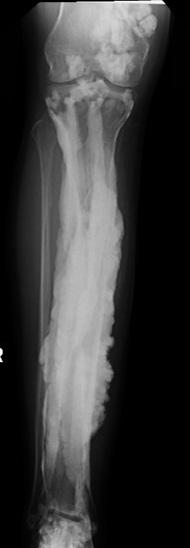

Melorheostosis of the Leg

image: An x-ray image of a patient with melorheostosis shows excess bone formation, likened to dripping candle wax. view more

Researchers at the National Institutes of Health worked with 15 patients from around the world to uncover a genetic basis of "dripping candle wax" bone disease. The rare disorder, known as melorheostosis, causes excess bone formation that resembles dripping candle wax on x-rays. The results, appearing in Nature Communications, offer potential treatment targets for this rare disease, provide important clues about bone development, and may lead to insights about fracture healing and osteoporosis.